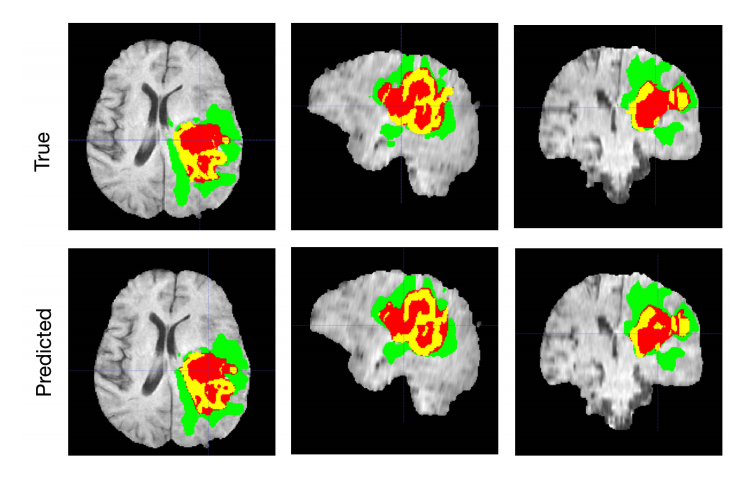

- Segmentation

- Object + Outline

- 객체의 경계 표시

- 알고리즘 : FCN, UNET, DeepLab

- 대표적인 예로 암의 위치를 파악하는 데에 쓰인다.